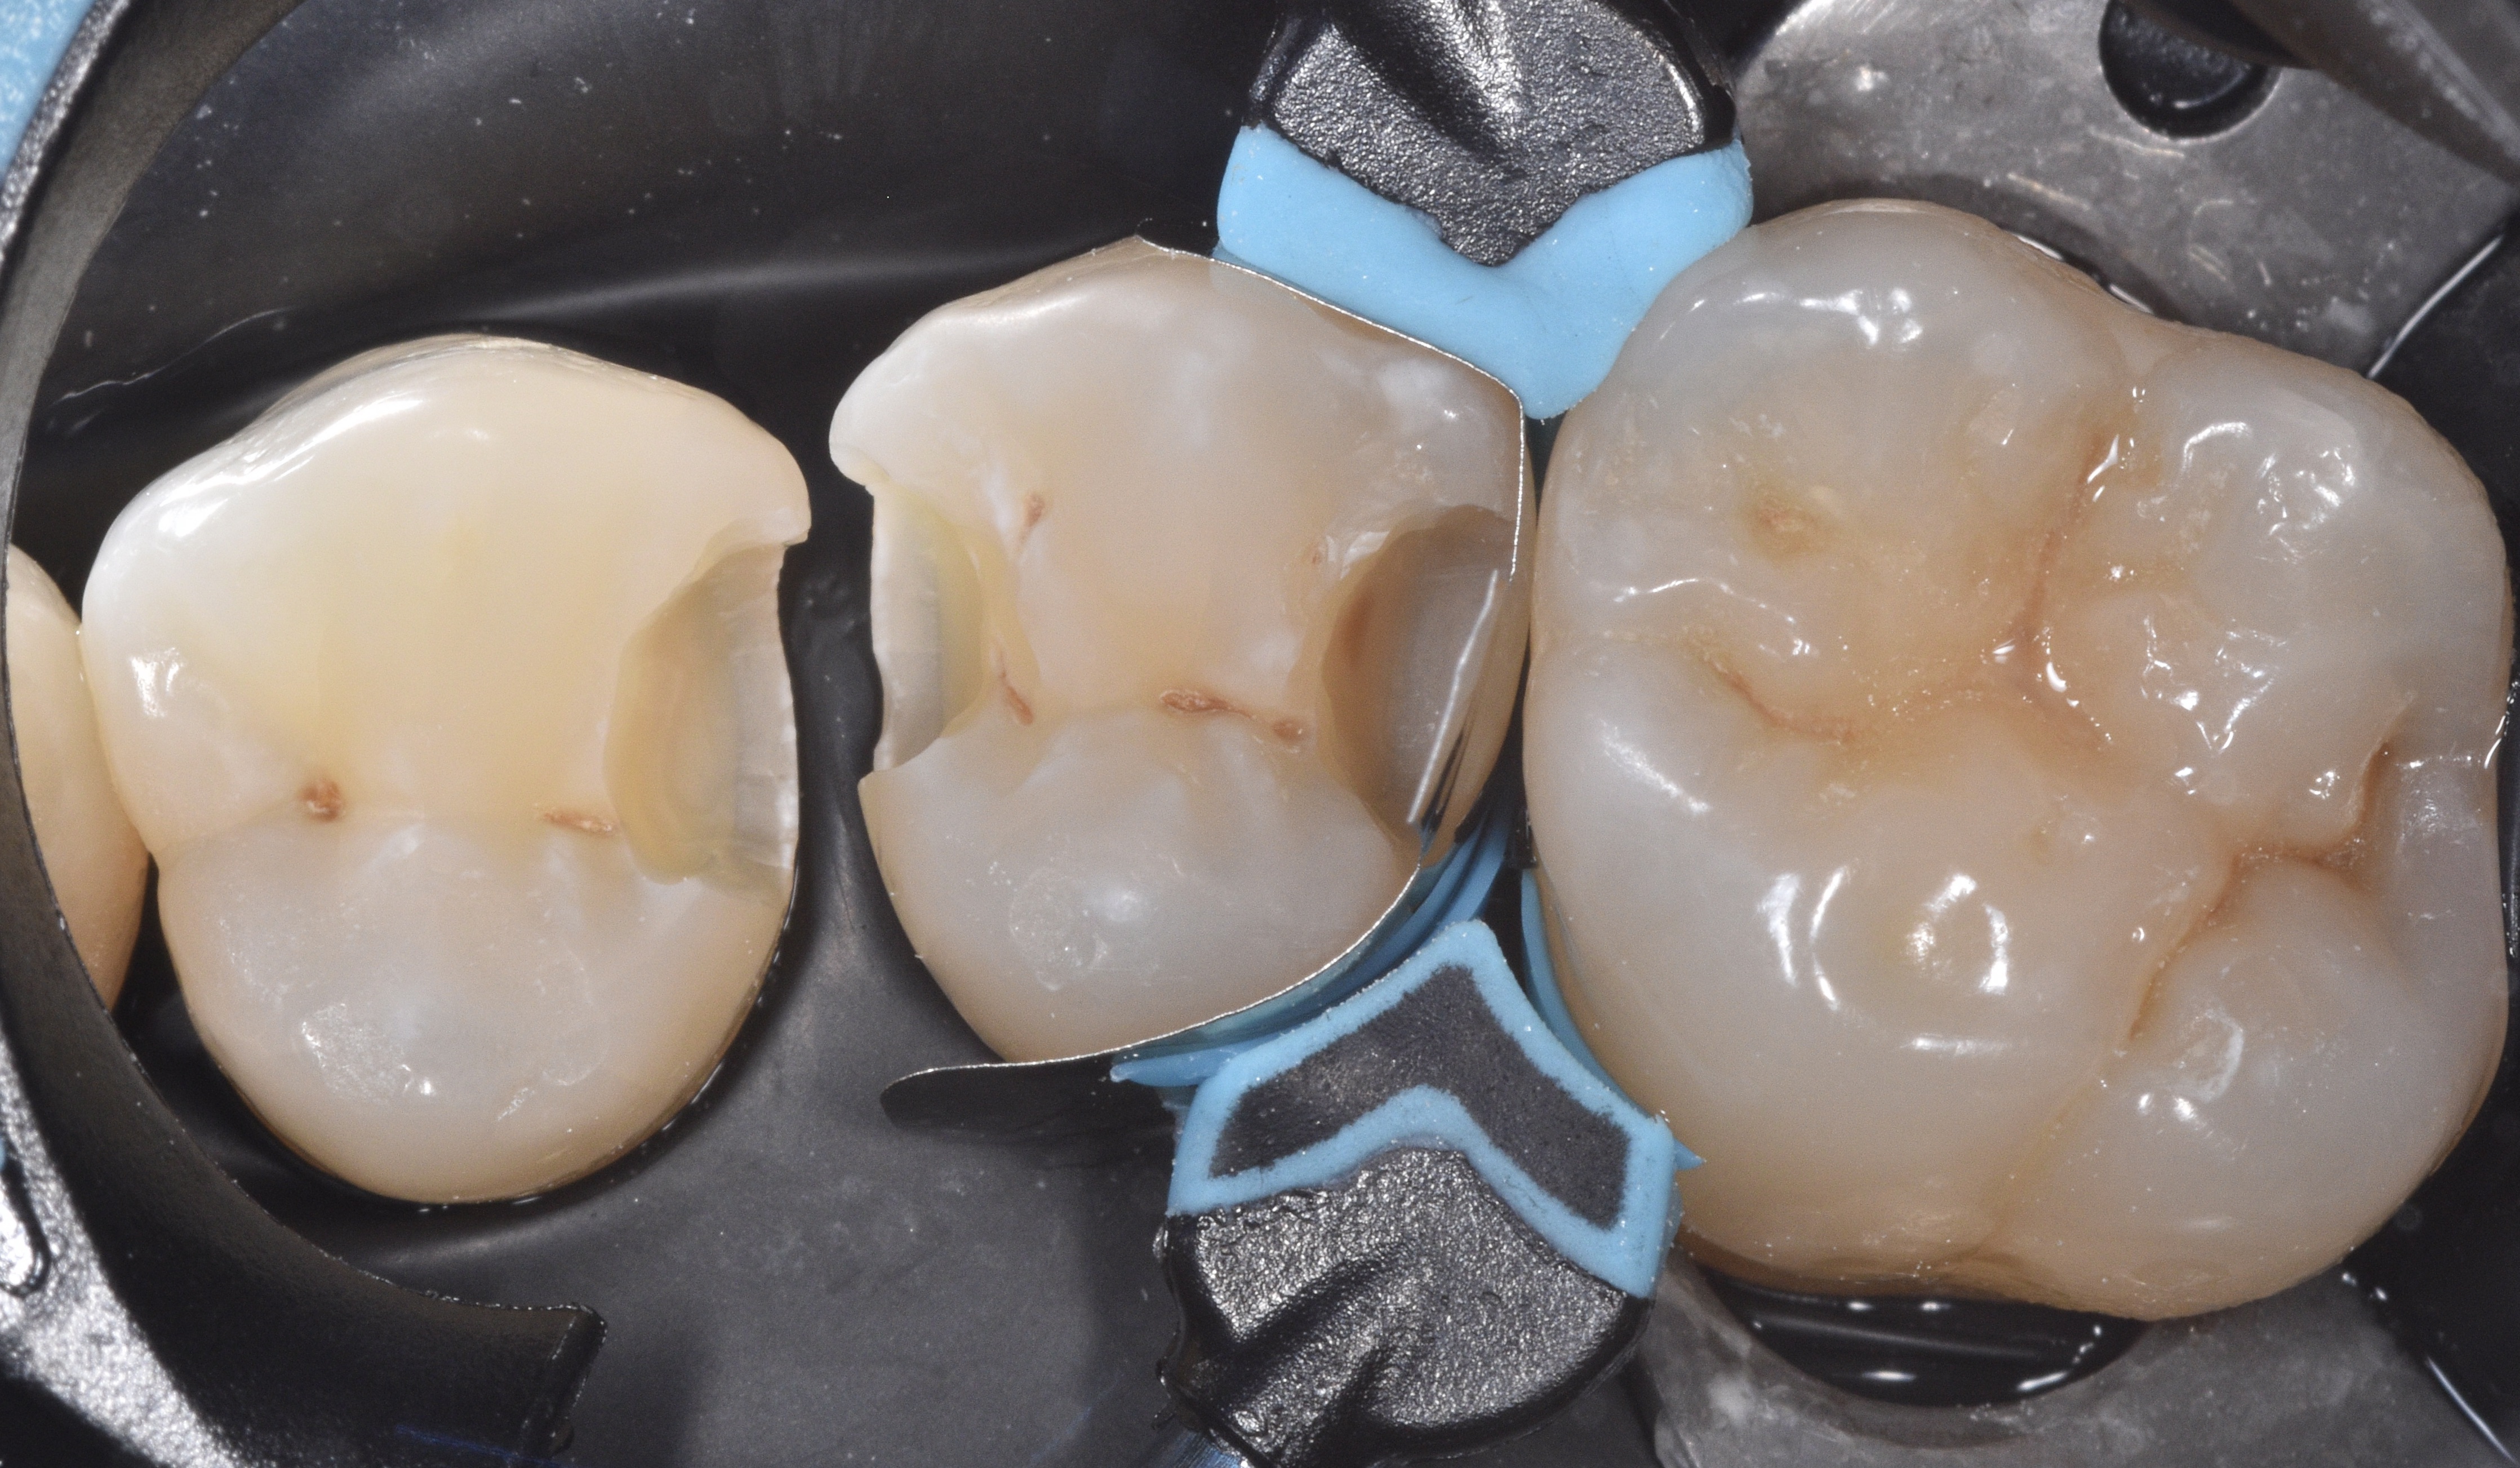

We remove the sectional matrix system and place it in between teeth #12-13 to restore both preparations simultaneously (Figure 7). See how the Quad wedge split tip contours the bands even prior to placing the ring.

After completing the same adhesive steps as before we built both proximal walls between #12-13 (Figure 9) and continued to restore the occlusal surface (Figure 10)